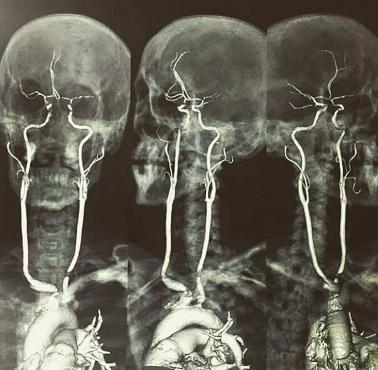

Zdjęcie obrazu rezonansu magnetycznego uchwycony, gdy matka całuje swojego zaledwie dwumiesięcznego syna. Pocałunek mamy na czole chłopca, wywołał natychmiastową reakcję w jego mózgu.